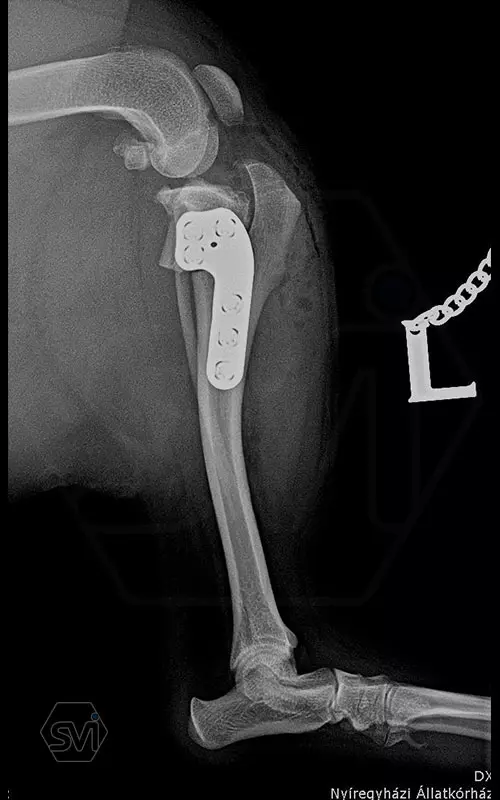

The cranial cruciate ligament rupture of a 7-year-old 8 kg active mix dog was solved a year ago with a precontured polyaxial 2.4mm system, now the other leg has been laid out, and this plate was used here as well. The stability of the system, its fit to the bone and the good healing can be measured nicely on the 1-year control X-ray.

The 2.4 system is great to use where the 2.0mm is already small, but the 2.7mm is still very big. This is a populous family of 6-14 kg dogs, according to our own data for 2021, the 2.4 mm size makes up 14% of all TPLO surgeries!

Recommended for R12 or R15 blades.

A mini-hole on the proximal piece of the plate and a temporarily used 1.0 mm K-wire drilled through it facilitate installation, as the plate has only a polyaxial hole. It is important that it is not necessary to tighten the screws with a hand-held screwdriver with high force, as is recommended for monoaxial systems, but it is sufficient to use the screwdriver with three fingers ("3 finger technique"), this force is sufficient for maximum fastening!